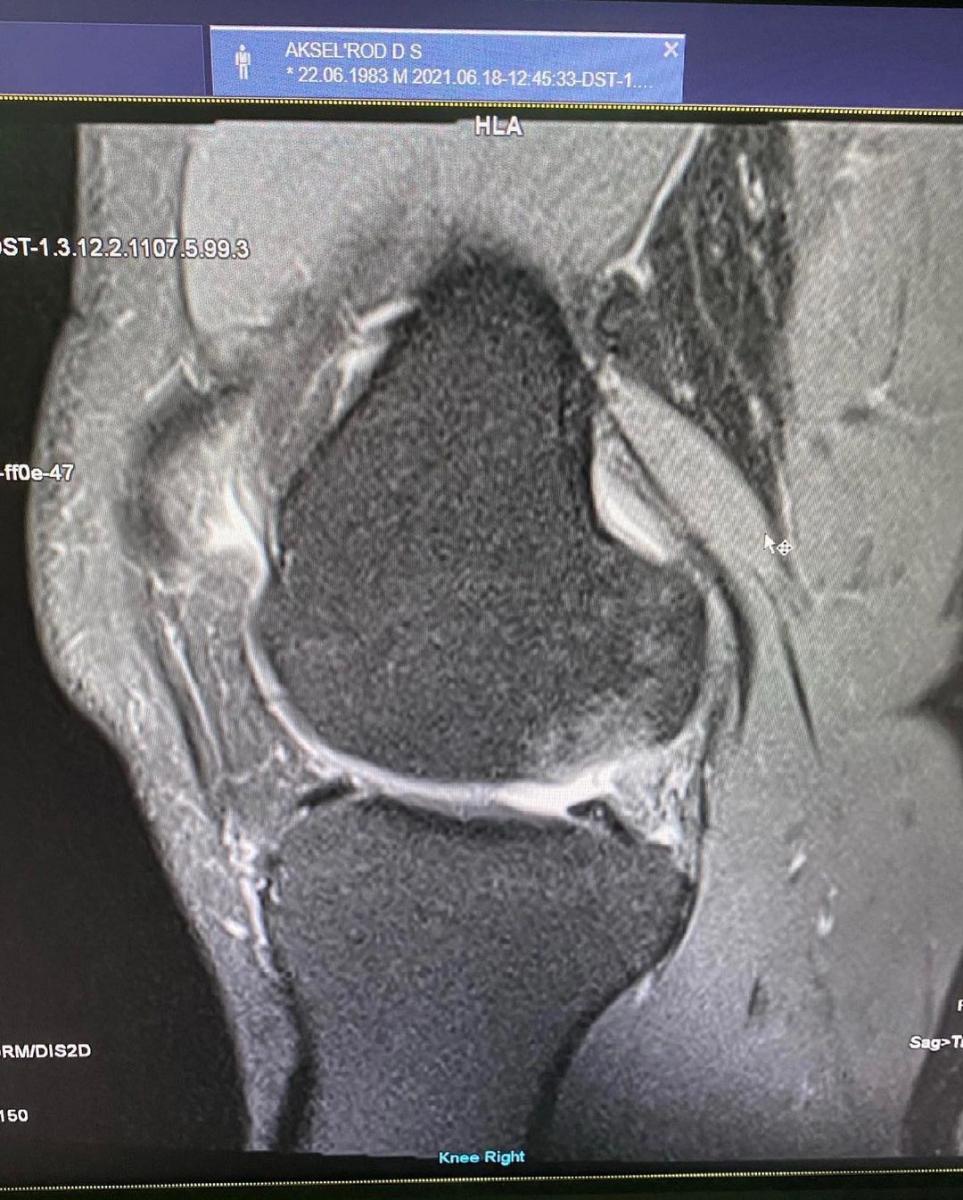

"Недавно я делал МРТ. Сначала я себе сам поставил диагноз. И это было ошибкой, конечно, там ничего из того, что я себе надумал, не было. Но мой врач сказал, что операция неизбежна и ее надо делать, если я хочу не то, что заниматься спортом, а вообще хотя бы ходить без лекарств", — поделился Дэвид.

Артист добавил МТР снимок коленного сустава, на котором связки подсвечены белым.

"Мне нужен ортез для того, чтобы я мог продолжать заниматься спортом и подготовить себя к операции. Тем самым сократить время реабилитации, который может длиться от трех до шести месяцев. Поэтому, пока я продолжаю свою послековидную реабилитацию, которая плавно переходит в процесс подготовки к операции моего коленного сустава и связок!", - добавил он.